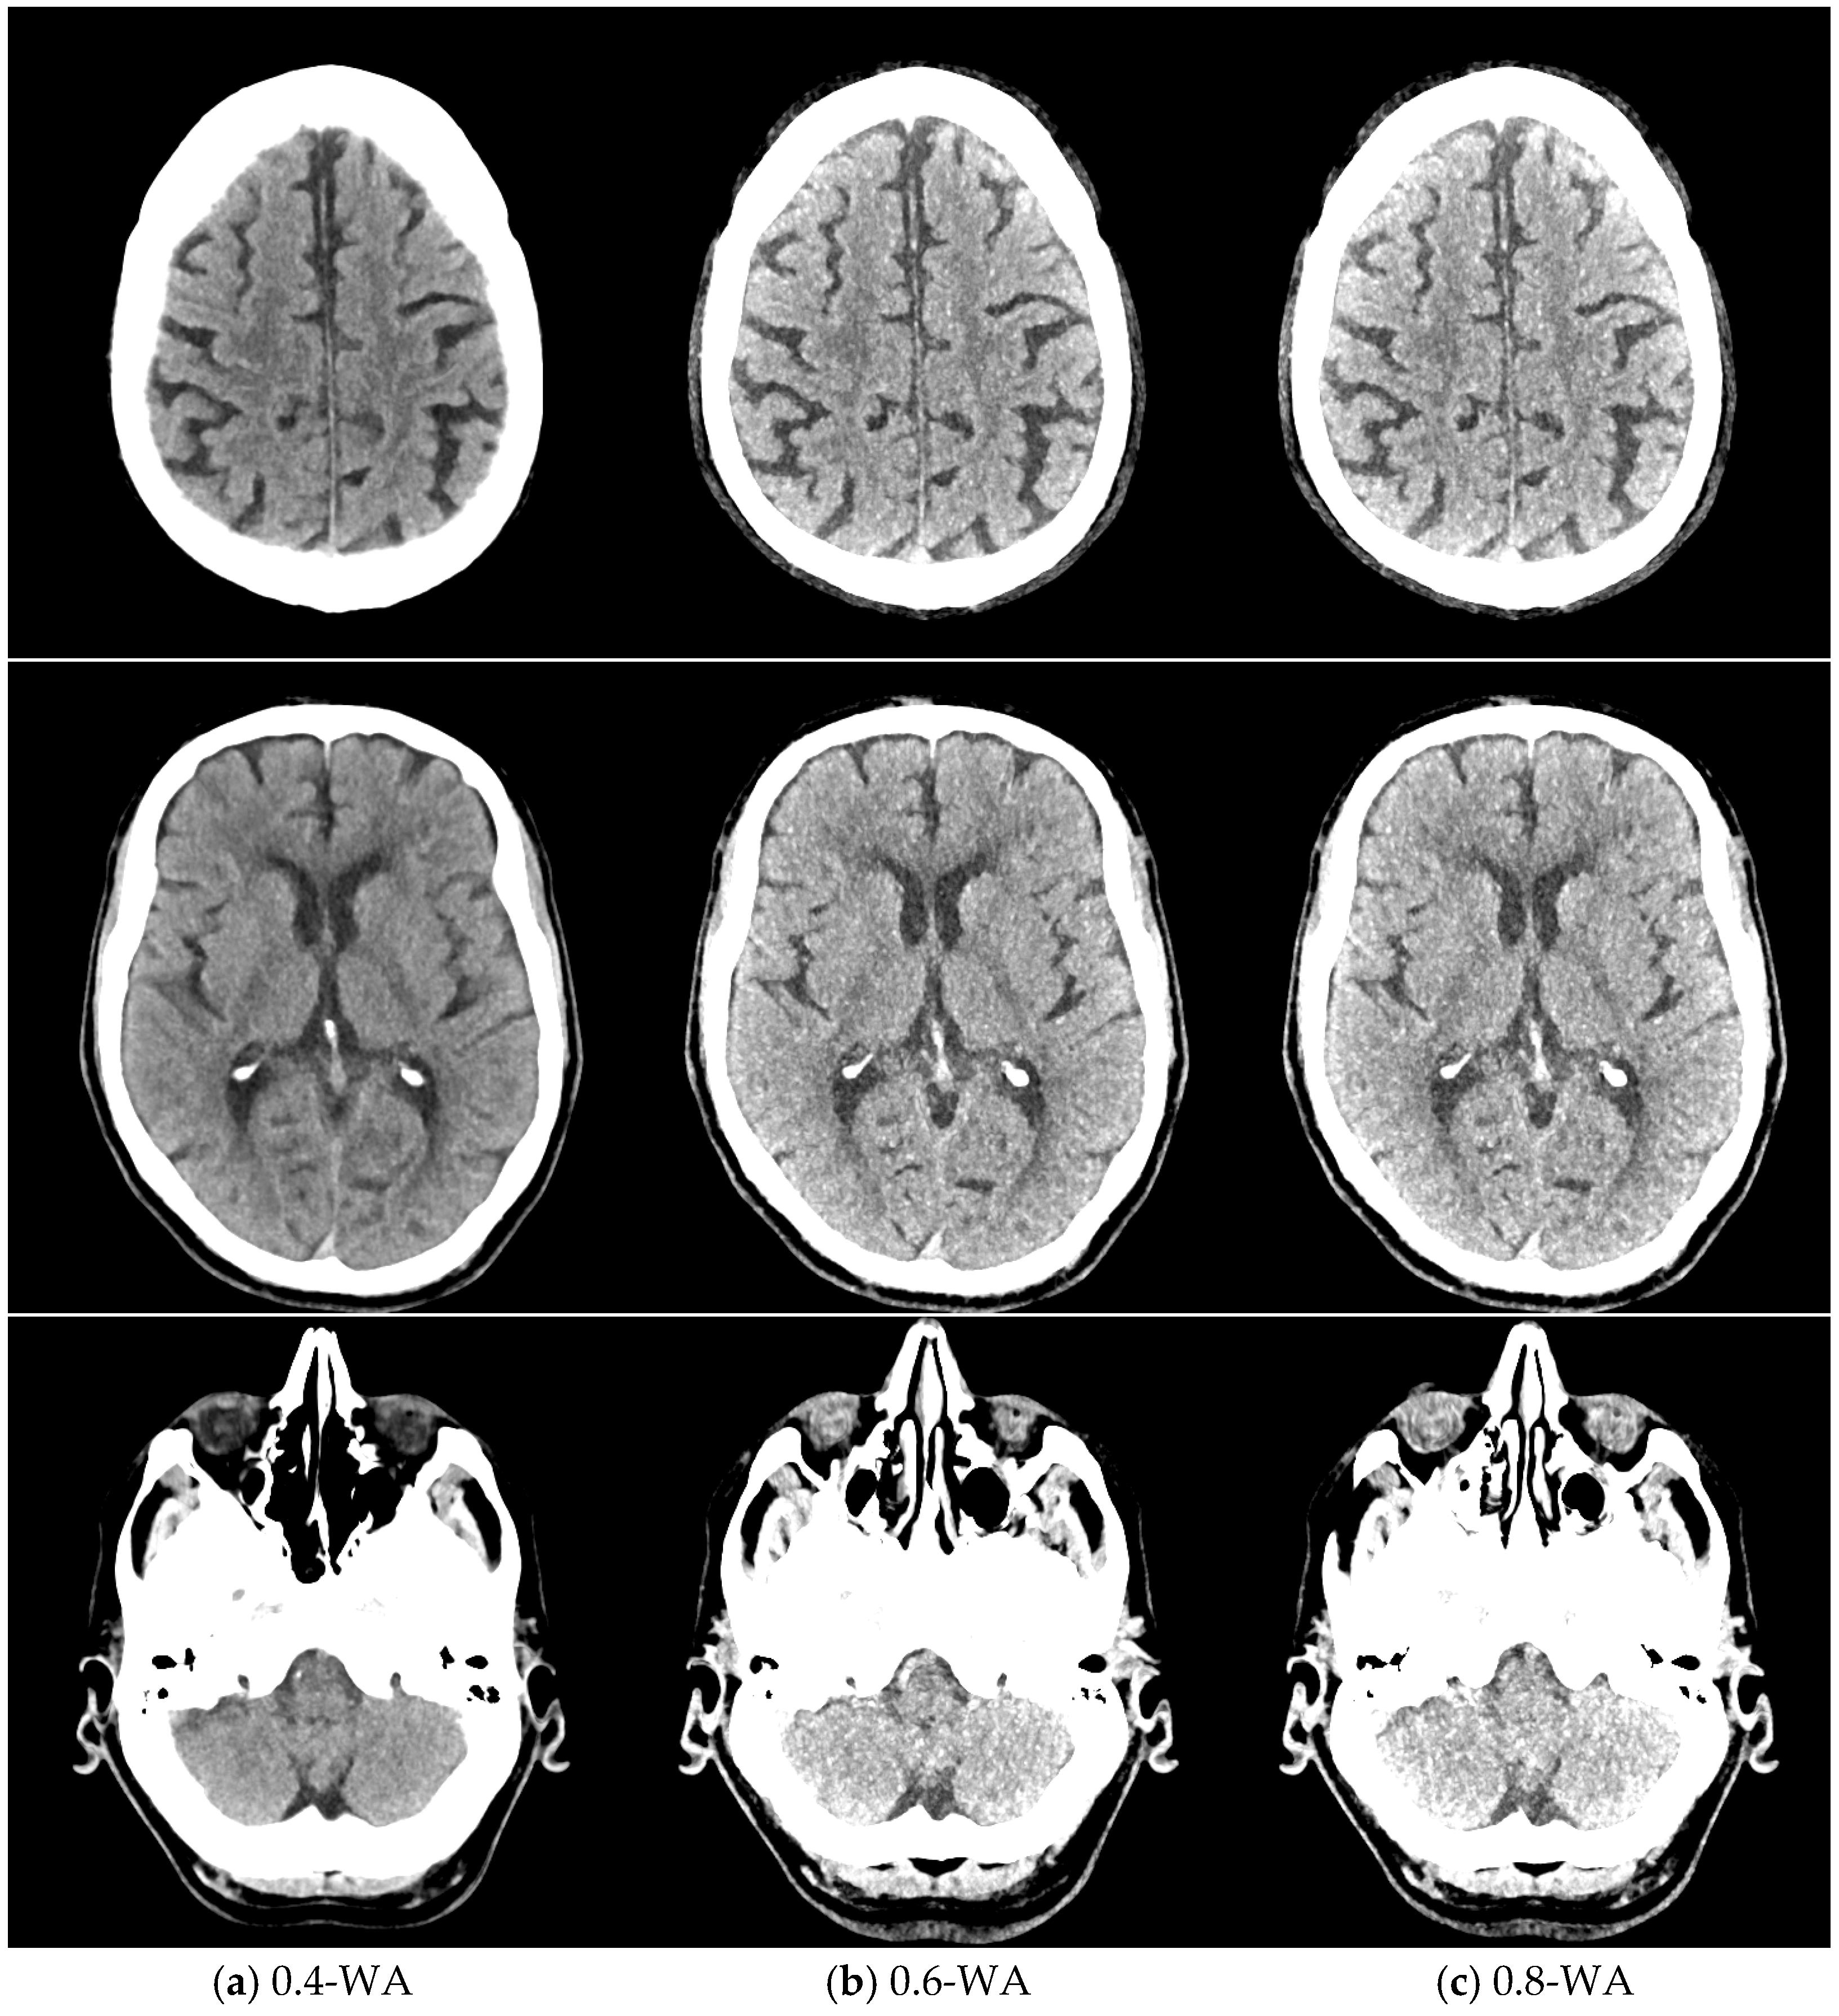

The qualitative assessment of the image quality of the 0.4-WA, 0.6-WA, and 0.8-WA patient reconstructions (Figure 5) was performed according to the methodology described in Section 2.1.3. of the phantom study.

Figure 5.

Weighted average (WA) image datasets of the brain with different weighting factors—0.4 (a), 0.6 (b), and 0.8 (c) of the same patient at the level of the frontoparietal lobe, basal ganglia, and posterior fossa. All images are displayed with the same window width and level (WW 80, WL 35).

The results of the qualitative analysis and image quality scores for all three readers, along with the results of the Friedman test with Bonferroni correction, are summarized in Table 6 and Figure 11. All readers found statistically significant differences in noise, SCA, and PFAI between all three WA image datasets. Reader 1’s results showed no significant differences in GM–WM contrast between the 0.4-WA and 0.6-WA images (p = 0.086), while reader 3 found no significant difference between the 0.4-WA and 0.8-WA reconstructions (p = 0.161). All three readers found that the overall IQ of 0.8-WA images was significantly lower compared to the 0.4-WA and 0.6-WA reconstructions. Two readers rated the overall IQ highest for 0.6-WA, with statistically significant differences compared to 0.4-WA and 0.8-WA (both p < 0.001). Reader 1 found the overall IQ of the 0.4-WA and 0.6-WA reconstructions equally superior to that of 0.8-WA (p < 0.001).

This study shows that the image quality of 0.6-WA image reconstructions is superior to the 0.4-WA images, which are generally recommended for the routine evaluation of non-contrast DECT of the brain. Quantitative and subjective analysis of phantom and patient images revealed that the optimal balance between GM–WM CNR, noise, and artifacts is achieved in WA reconstructions with 60% to 40% contribution of low-energy (80 kVp) and high-energy (140 kVp) datasets, respectively. While SECT provides an acceptable contrast-to-noise ratio, the 0.6-WA DECT reconstructions significantly outperformed the SECT proxy DECT reconstructions with 0.4 WF. This improved contrast between GM and WM increases the diagnostic accuracy of brain imaging, which is not as easily achieved with SECT.

Building on the phantom study, the patient study focused on 0.4-WA, 0.6-WA, and 0.8-WA image datasets. The quantitative analysis showed the same trend as in the phantom study—as expected, GM–WM CNR, SCA, and PFAI increased with higher WF. Although the absolute differences in CNR between the different WA image datasets are small, they are statistically significant and clinically relevant. Even small improvements in CNR can enhance diagnostic confidence, particularly in distinguishing subtle brain pathologies, as the inherent GM–WM contrast on CT imaging is small, with only a 5–10 HU difference in attenuation. Readers agreed that 0.6-WA reconstructions had the highest overall quality for image evaluation. We argue that a slight prevalence of low-energy data enhances GM–WM CNR while the contribution of high-energy data is still high enough to keep the artifacts at a reasonably low level. Although the routinely used 0.4-WA reconstructions, which are considered a proxy for standard SECT images at 120 kV, have fewer artifacts compared to 0.6-WA images, they are diagnostically inferior because they do not achieve sufficient GM–WM CNR, which is pivotal for detecting abnormalities in the brain tissue. On the other hand, although GM–WM CNR is higher in 0.8-WA images compared to 0.6-WA reconstructions, the artifacts affecting the analysis at the brain–bone interface (SCA) and posterior fossa (PFAI) significantly lower its overall diagnostic value. Moreover, all readers deemed 0.8-WA reconstructions to be significantly inferior to 0.4- and 0.6-WA images. These results are consistent with other studies that have shown that radiologists are more likely to prefer higher-contrast images, even at the expense of increased noise, over lower-contrast images with minimal noise artifacts [25,39].